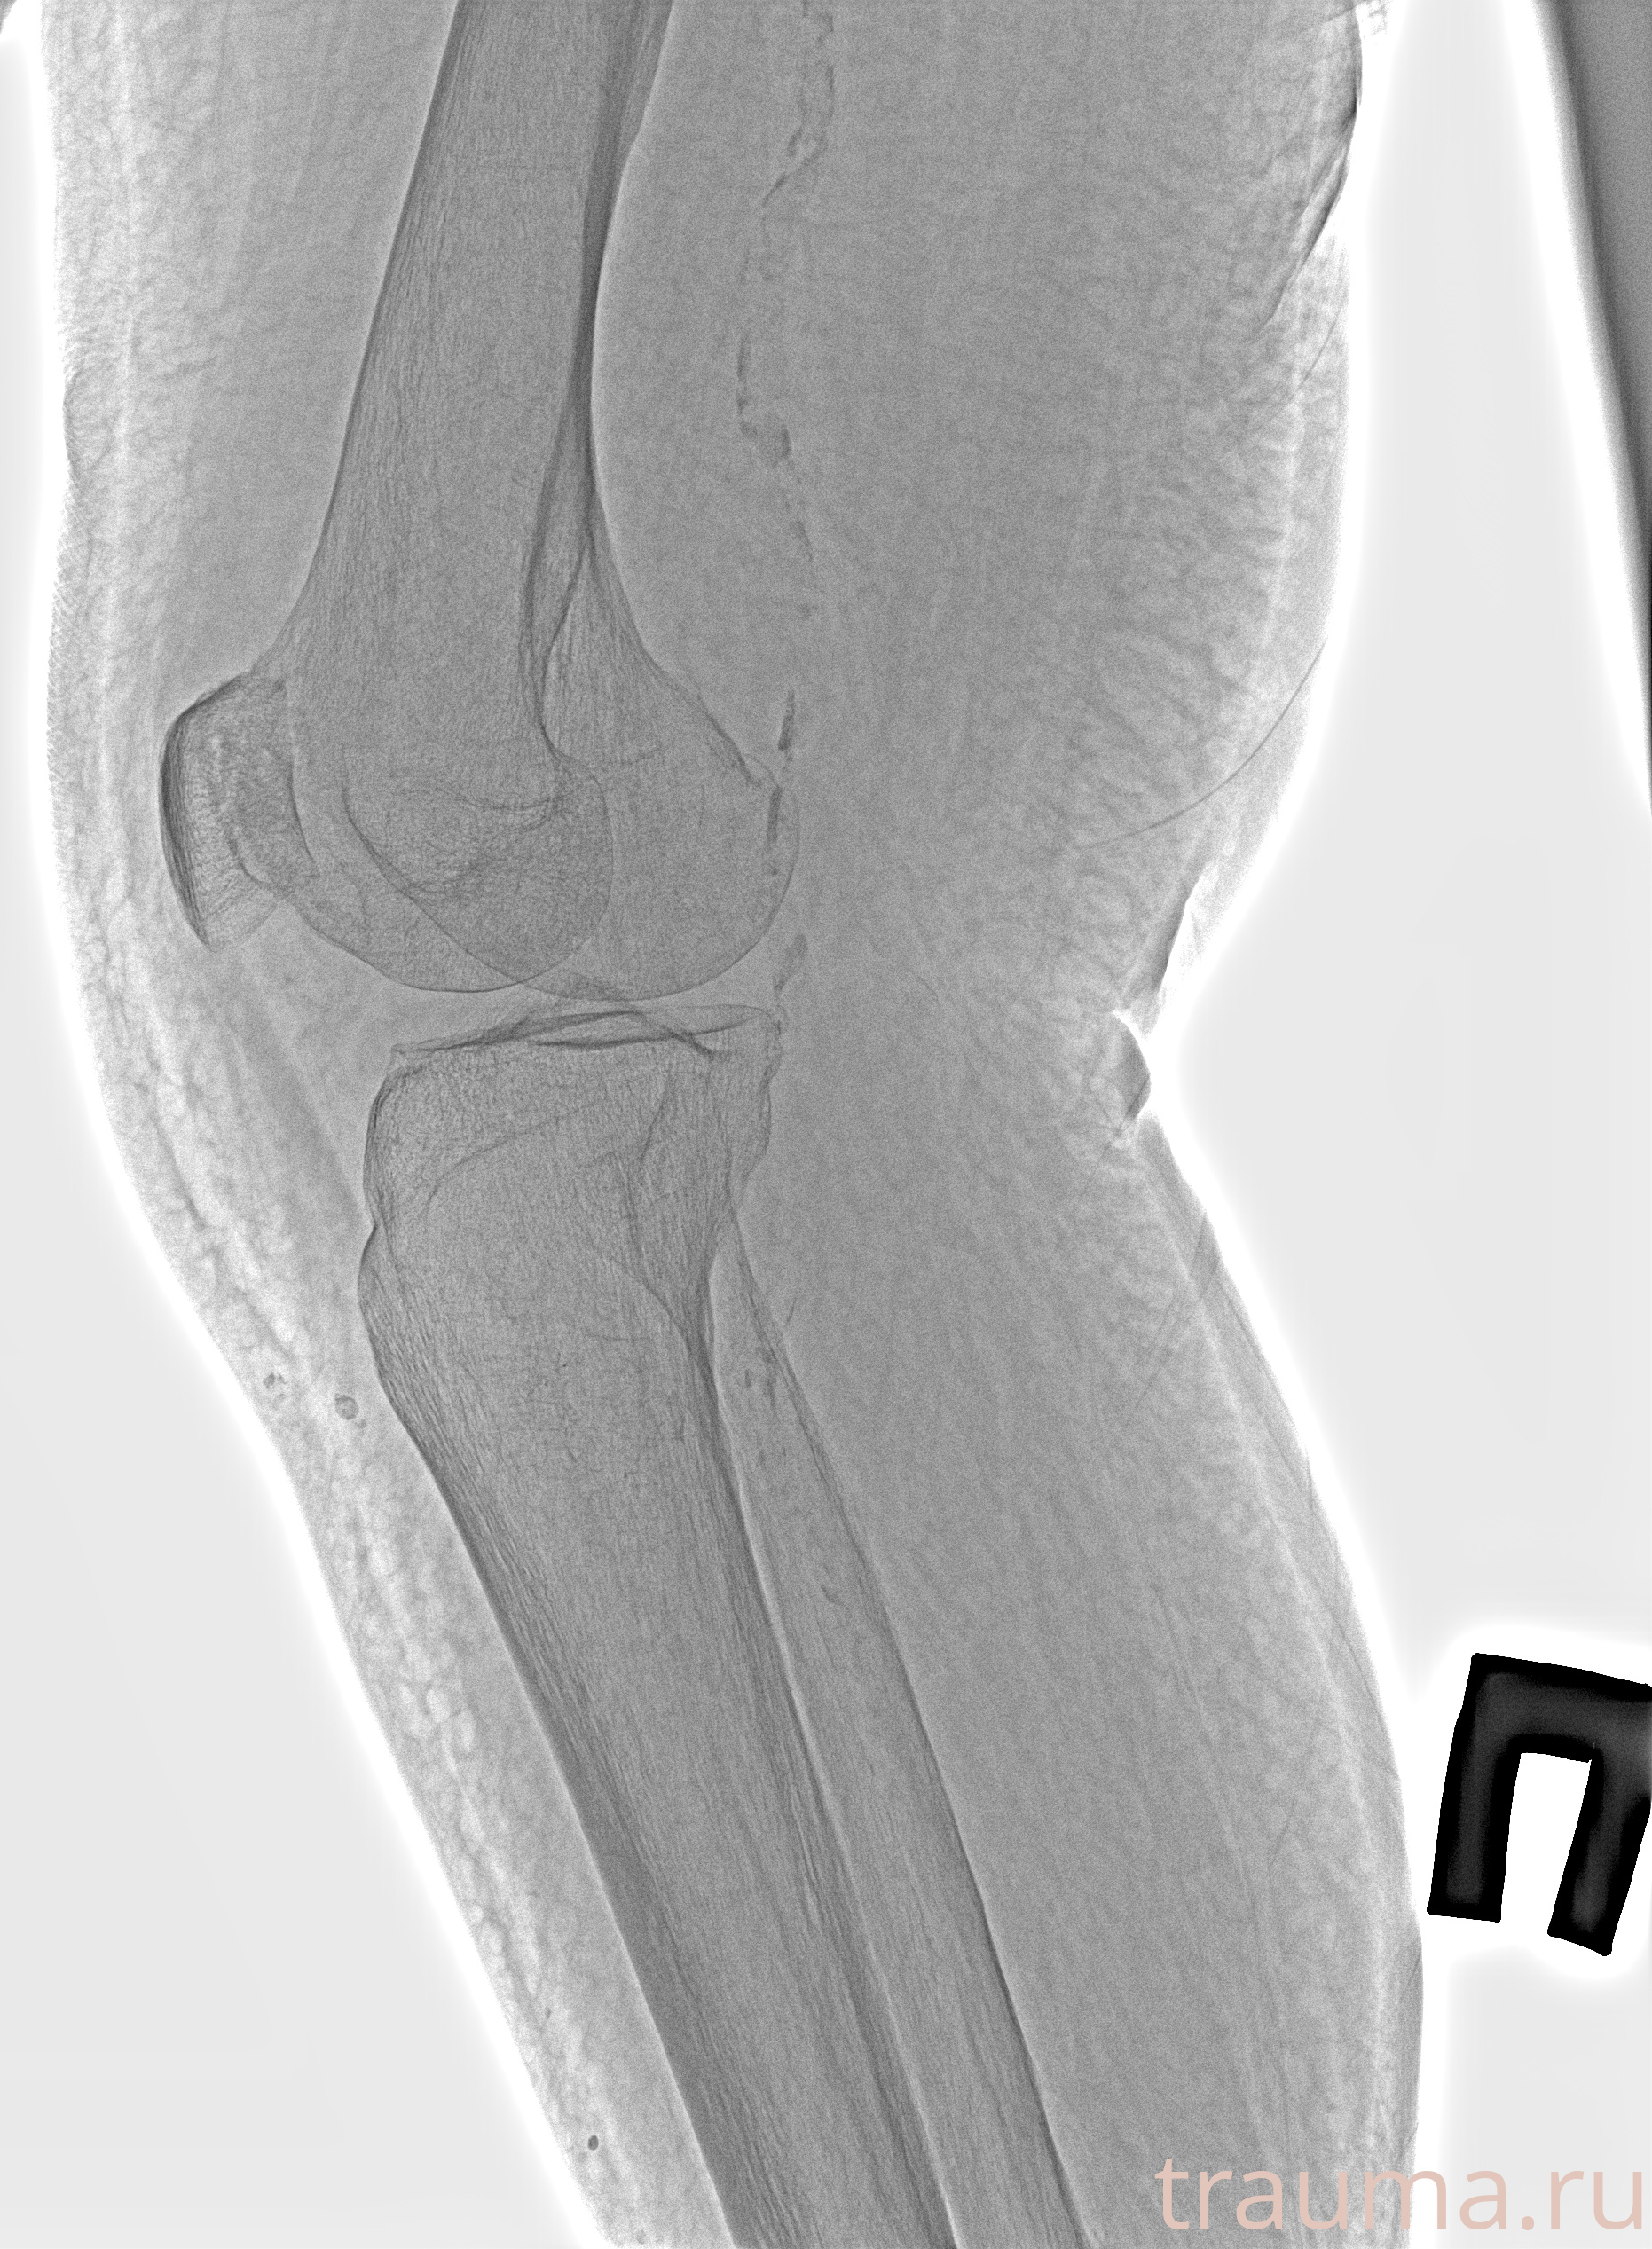

Рентген на дому: по вашему адресу приезжает врач-рентгенолог, травматолог-ортопед с мобильным рентгеновским аппаратом, проводит диагностику травмы или заболевания, делает необходимые рентгенограммы, дает рекомендации по дальнейшему лечению. Получить качественные снимки в домашних условиях возможно благодаря уникальной методике, разработанной МосРентген Центром для института  Склифосовского